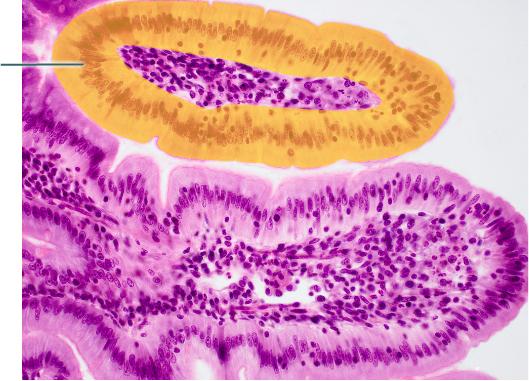

Name the tissue?

areolar

adipose

blood

bone

blood

Name the tissue

reticular

nerve

areolar

skeletal muscle

areolar

Which structure is highlighted?

simple columnar epithelium

microvilli

lamina propria of villus

villus

simple columnar epithelium